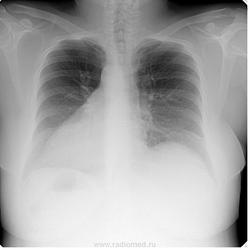

Контурное обызвествление протеза правой мол. железы.

Игорь Иванович, я утверждаю: 1. Видимое изображение протеза правой мол. железы отличается от такового левой и видно это невооруженным глазом. 2. Отличие проявляется в высокой плотности видимого контура протеза справа, при этом плотность и видимая ширина полоски контура по периметру протеза непостоянна, потому я и назвал "контур практически пунктирным" 3. Мне не известны процессы в нормальном организме, дающие такую картину, кроме обызвествления на границе с чужеродной тканью. 4. Крайне маловероятно, чтобы из двух парных изделий рук человеческих, применённых в одном организме одно имело структуру (конструкцию) значительно отличающуюся от другого и притом столь удачно имитирующую обызвествление. Что Вы оспариваете?

Для большей убедительности добавил снимки, сделанные на 1,5 года раньше. Там "пунктирность" заметнее.

Вот с этим можно согласиться. Про скиалогию. Обызвествление происходит при осложнениях инфекция или гематома.

1.Как только под кожу устанавливается имплантат, вокруг него формируется фиброзная ткань в виде капсулы. Ее формирование является частью нормального процесса заживления раны, которое обычно происходит в течение первых нескольких месяцев после операции. В 15% случаев эта капсула может быть болезненной и плотной, деформируя молочную железу . В случае применения лучевой терапии риск формирования рубцовой капсулы возрастает на 40 – 50 %. Для профилактики образован такой рубцовой ткани рекомендуется массаж и физические упражнения.

2.Еще одним из фактов, которые очень важно принять во внимание пациенткам, выбирающим грудные имплантаты – это то, что этот вид реконструкции молочной железы затрудняет в дальнейшем диагностику опухолей. Этому может способствовать тот факт, что фиброзная (рубцовая) капсула, которая образуется вокруг имплантата, может со временем пропитаться солями кальция (так называемая кальцификация).

3.Многие специалисты считают, однако, что, действительно, при использовании маммографии у женщин c имплантатами молочной железы, кальцификация может возникнуть в фиброзной капсуле, окружающей протез, но при этом она не ставит под угрозу маммографическое исследование. Как правило, обызвествления не являются характерной чертой кальцификации, которая ассоциируется с озлокачествлениями, хотя иногда одно можно принять за другое. В литературе не опубликовано сообщений, которые подтвердили бы документально пропущенные или запоздалые диагнозы в связи с наличием кальцифицированной капсулы.